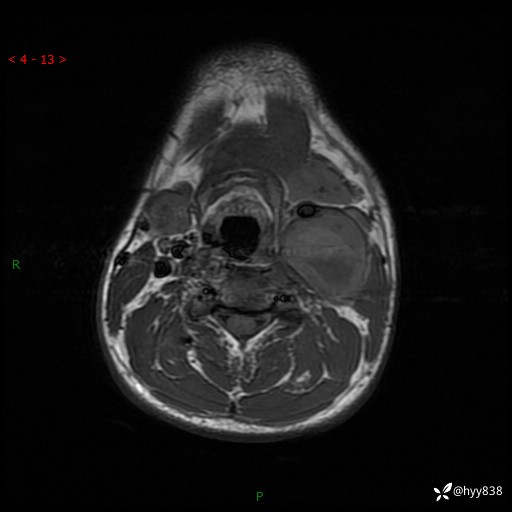

年轻小伙,发现左侧颈部肿物3年余,逐渐增大---结果公布~

现病史:患者约3年前因感冒发现左侧颈部长一肿物,约半个鸡蛋大小,无明显疼痛及其他不适,一直未行特殊处理。3个月前发现左侧颈部肿物变大,随后至当地市第二人民医院耳鼻喉科行左侧颈部彩超示:左侧颈部囊实混合性包块;喉部MPR示:左侧胸锁乳突肌内前方占位,累及左侧喉旁间隙,建议增强扫描。建议手术治疗。患者考虑。随后至我院肿瘤科就诊,行细胞学穿刺示:考虑血管源性肿瘤可能,建议进一步检查。建议至我院口腔科就诊,行颌面部MRI示:左侧颌下腺后方团状异常信号灶,建议增强。建议手术治疗。为求进一步治疗,门诊以“左侧颈部肿物”收入院。 起病以来,患者神志清、精神良好,饮食睡眠良好,大小便正常,体重未见明显变化。

颈部MRI平扫+增强